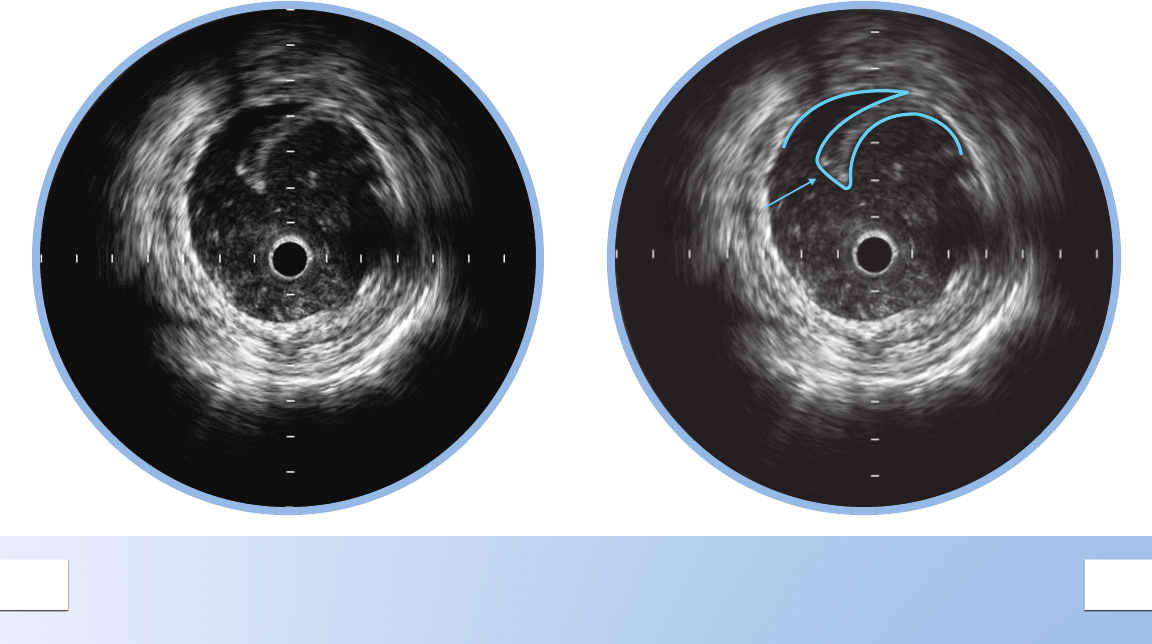

NORMAL VESSEL

In a normal vessel, the lumen border is almost

indistinguishable from the vessel border. While

IVUS allows visualization of vessel and lumen,

angiograms only provide a shadow of the

lumen. In patients with diffuse disease, relying

on the angiogram alone can potentially lead to

underestimation of stenosis.

The lumen border is drawn inside the intima

or plaque.

The intimal layer is normally not seen unless it has

begun to thicken.

The catheter mask (red area) indicates the location

of the ultrasound transducer.